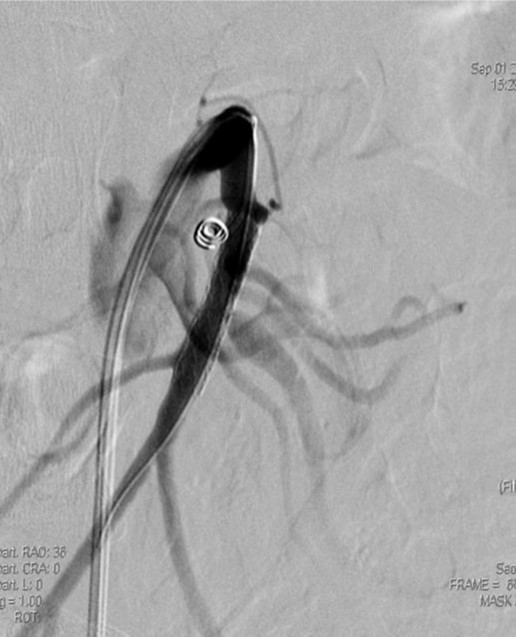

2009년 3월 복부 CT에서 SMA 기시부 하방 2cm 부위부터 5cm 길이의 편심성 혈전이 관찰되고 있으며 혈전이 있는 부위의 동맥 직경이 커져 있음(Fig. 1). 대동맥이나 분지 동맥에 동맥경화증의 소견은 관찰되지 않으며 심장초음파 및 심전도 검사에서 혈전이나 심방 세동은 없었음. CT 소견과 증상을 기준으로 spontaneous isolated SMA dissection으로 진단하였으며 창자의 허혈 소견이 보이지 않고 통증도 악화되지 않아 보존적 치료를 하였음. 2009년 6월 추적 CT에서 false lumen내 대부분의 혈전은 소실되었으나 SMA 기시부 5cm 하방 부위에는 국소적 혈전을 동반한 saccular pseudoaneurysm이 관찰됨. 2009년 8월 시행한 추적 CT에서 pseudoaneurysm의 직경이 2mm 증가함 (Fig. 2). 2009년 9월 시행한 혈관 조영술에서 saccular pseudoaneurysm이 SMA 기시부 5cm 하방부위에 관찰되며 SMA의 국소적 협착이 관찰됨 (Fig. 3). 스텐트와 코일을 이용한 혈관 내 치료 후 시행한 혈관 조영술에서 SMA의 국소적 협착과 pseudoaneurysm은 소실됨 (Fig. 4). 시술 3개 월 후 시행한 추적 CT에서 pseudoaneurysm은 완전히 소실되었으며 SMA는 정상소견을 보임(Fig. 5).

Right femoral artery를 천자하여 superior mesenteric artery에 7-Fr guiding catheter(Cordis, FL, USA)를 위치시킨 후 시행한 혈관 조영술에서 SMA dissection 부위 true lumen의 협착과 동반된 pseudoaneurysm이 관찰됨, 협착된 SMA의 true lumen내에 6mm 직경, 29mm 길이의 balloon expandible stent(Genesis, Cordis, FL, USA)를 설치함.

스텐트 설치 후 협착은 소실되었으나 pseudoaneurysm은 소실되지 않고 크기만 작아짐. 스텐트의 철망을 통해 2.4 Fr microcatheter(Progreat, Terumo, Tokyo, Japan)를 pseudoaneurysm내에 위치시킨 다음 5mm microcoil (Cook, Bloomington, IN) 1개를 삽입함. 시술 후 시행한 혈관 조영술에서 SMA 협착과 pseudoaneurysm은 완전히 소실되었으며 추적 관찰기간 동안 재발 소견은 보이지 않음.

Fig. 4. A

Fig. 4. A. The size of psedoaneurysm is decreased, but still noted after stent placement in the superior mesenteric artery.

Fig. 4. B

B. After insertion of microcatheter in the sac of pseudoaneurysm through the mesh of stent, a 5mm diameter microcoil is placed in the sac.

Fig. 4. C

C. Completion angiography shows improvement of pseudoaneurysm and stenosis in the superior mesenteric artery.